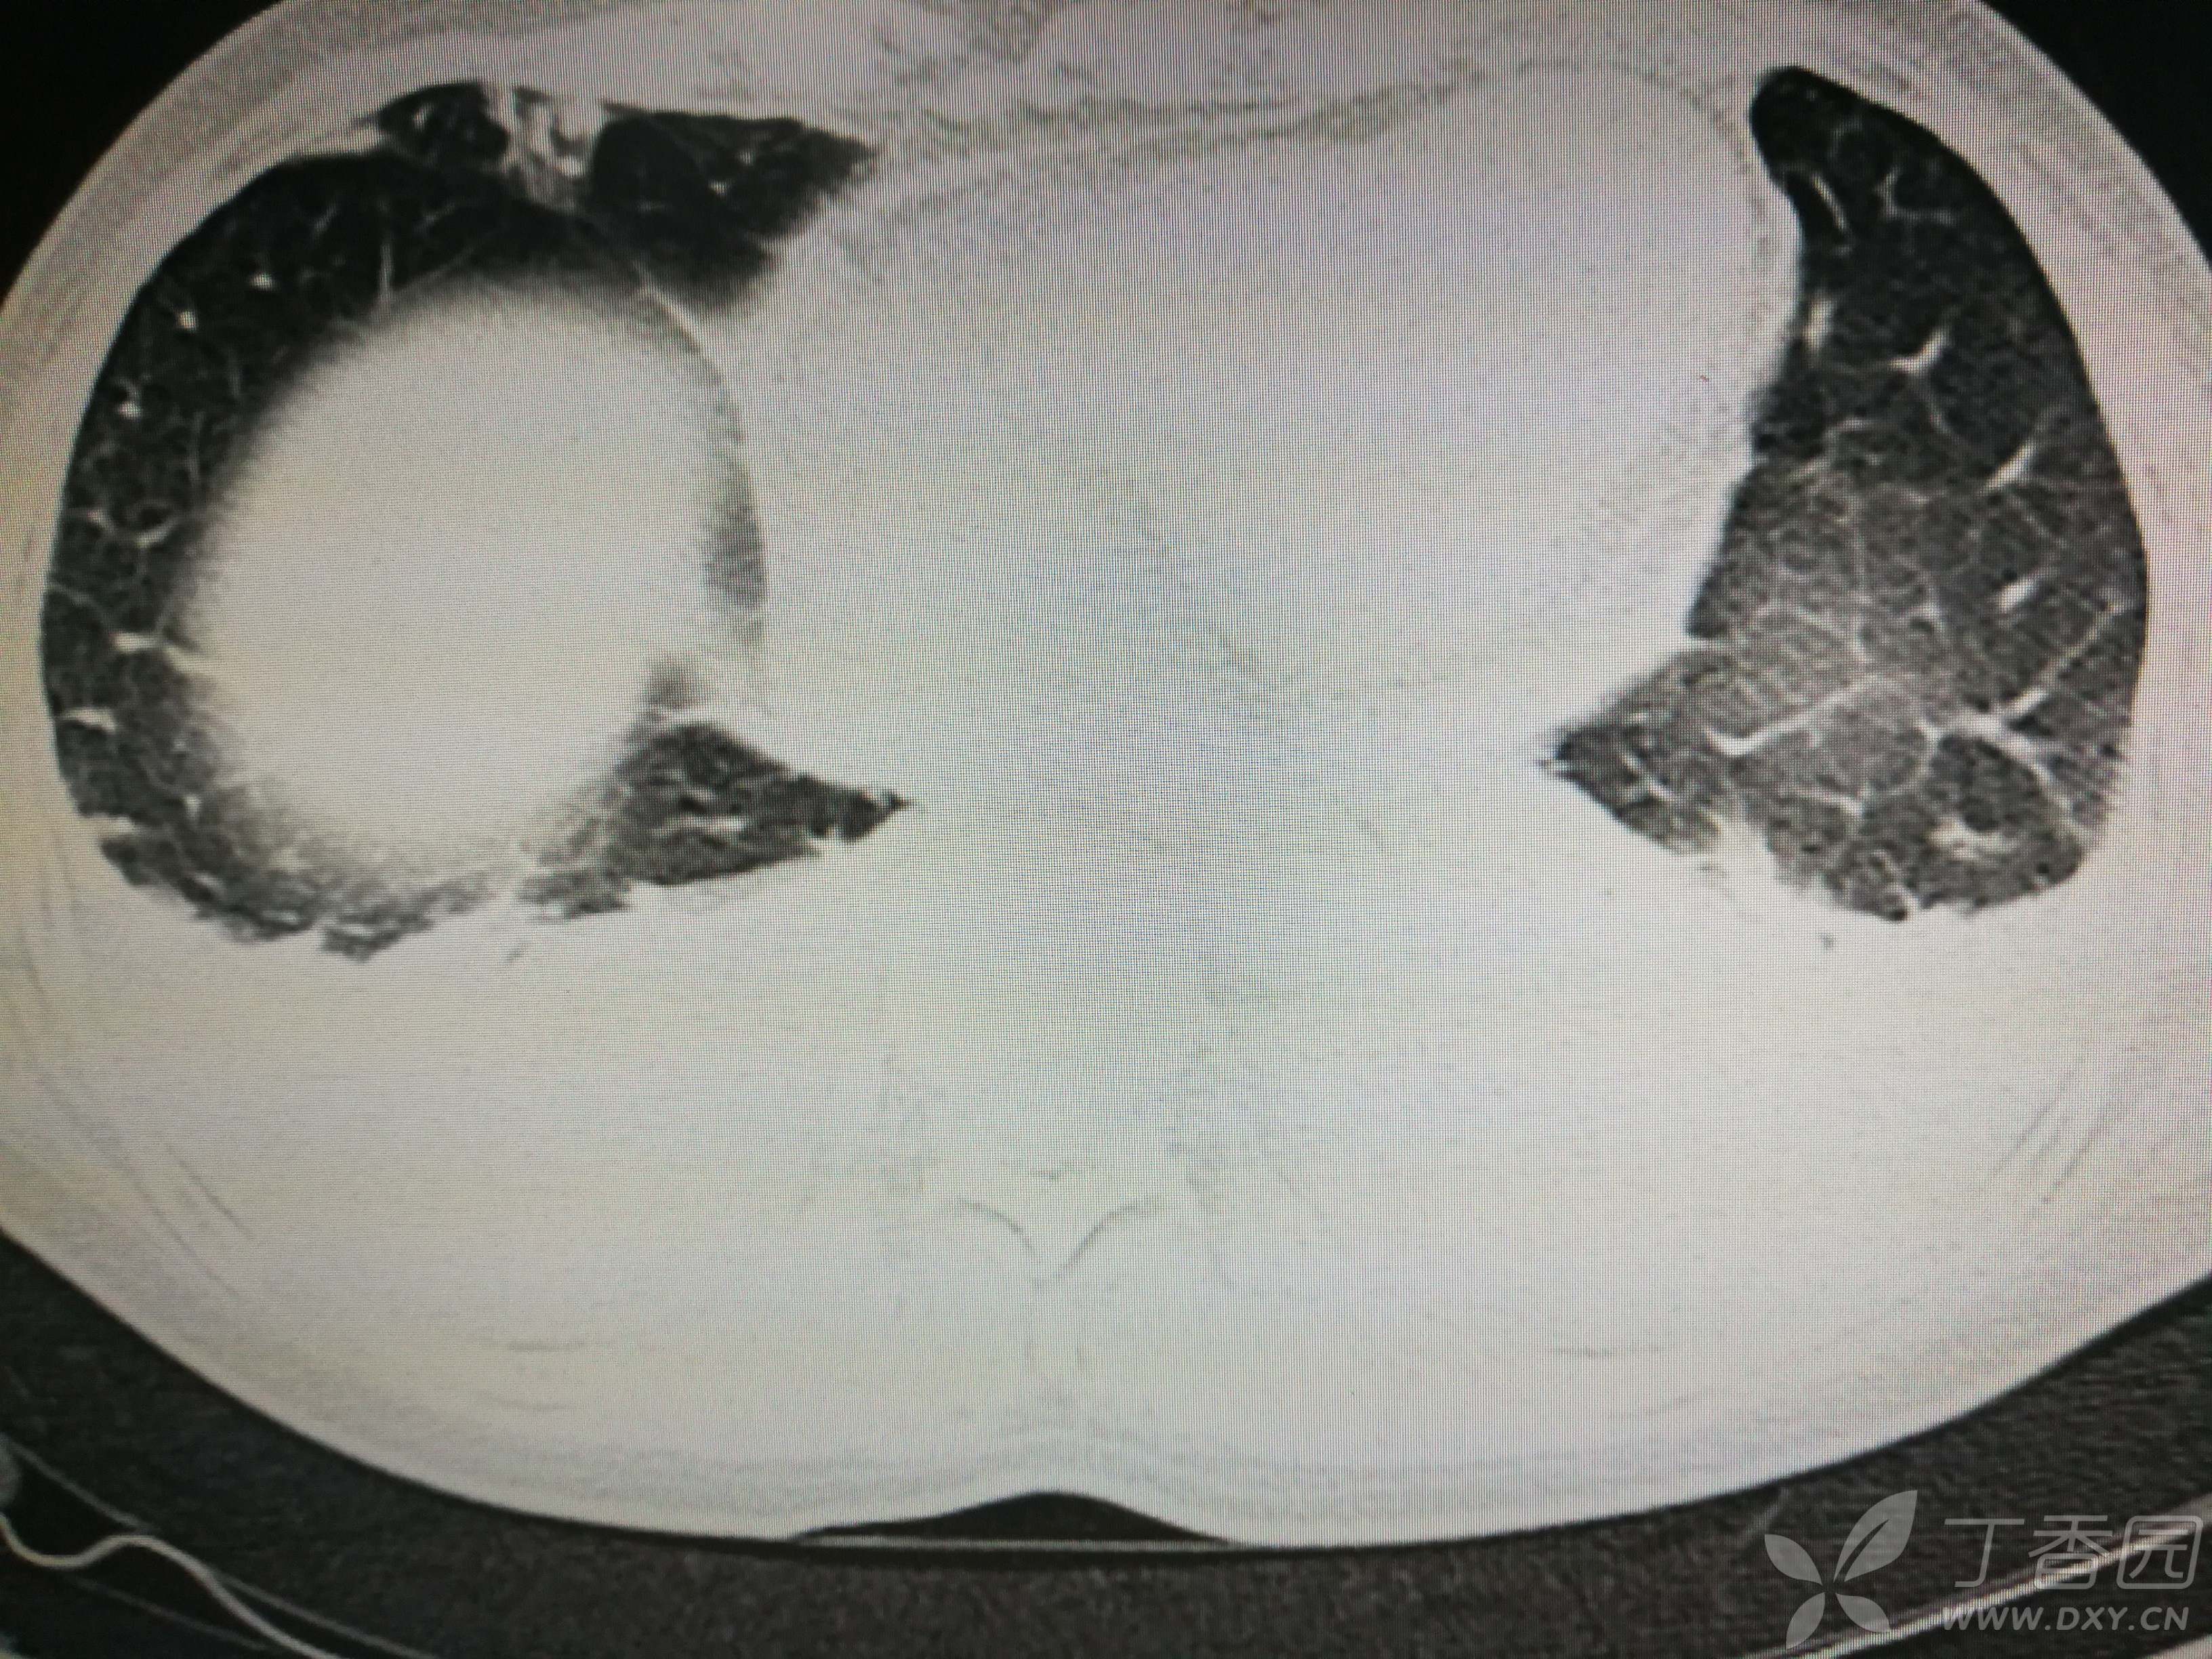

给予低分子肝素钙针抗凝、七叶皂苷钠针消肿及骨牵引固定等等治疗。入院后第四天行“左侧股骨下段骨折切开复位内固定术”(术前查双下肢彩超:双下肢深静脉血流通畅),手术顺利,术后予预防感染、预防血栓形成等治疗。术后患者无明显发热,生命体征平稳。术后第四天复查血常规:白细胞13.4×109/L,血红蛋白84g/L,血小板在正常范围。生化:白蛋白35.7g/L,余无明显异常。当天,患者开始出现轻度胸闷气急,可耐受。术后第五天患者胸闷气急加重,无胸痛,无背痛,无咯血,无意识障碍,无头晕头痛,无恶心呕吐等,急查凝血功能:纤维蛋白原降解产物12mg/L,D二聚体4000ug/L,余无明显异常。查动脉血气分析:pH7.52,氧分压62mmHg,二氧化碳分压30mmHg,碱剩余1.8mmol/L,乳酸1.0mm/L,血红蛋白86g/L。查胸部CT见下(先视频后图片):